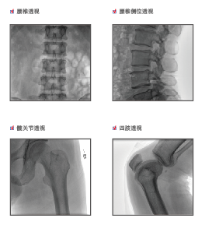

普爱医疗是专业从事平板小C生产、研发、售后为一体的厂家,目前我们应用在国内很多医院的一款PLX118F平板C形臂,它是一台集光、机、图像处理技术为一体的带数字减影血管造影功能(DSA)的可移动式X光机,该设备占地面积小、图像清晰、定位精准、辐射剂量小,是疼痛科医生的可靠眼睛,对于疼痛介入手术的精准化治疗、满足患者对慢性疼痛治疗需求提供了有利条件。